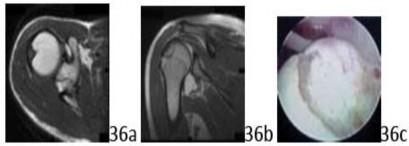

17. # 36a 36b 36c An active 45-year-old man sustained an acute traumatic anteroinferior dislocation. MRI scans and an arthroscopic view are shown in Figures 36a through 36c. The lesion represents compressive injury to which of the following structures?

3. # Posterosuperior humeral head

5. # Central portion of the humeral head

DISCUSSION: During an anteroinferior dislocation, the posterosuperior portion of the humeral head impacts the inferior rim of the glenoid, resulting in an impaction injury. This lesion is classically referred to as a Hill-Sachs lesion. The Preferred Response to Question # 36 is 3.